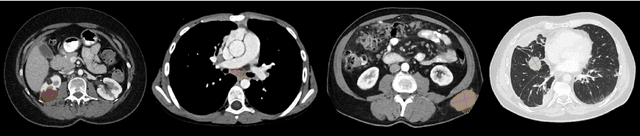

Abstract:Size measurements of tumor manifestations on follow-up CT examinations are crucial for evaluating treatment outcomes in cancer patients. Efficient lesion segmentation can speed up these radiological workflows. While numerous benchmarks and challenges address lesion segmentation in specific organs like the liver, kidneys, and lungs, the larger variety of lesion types encountered in clinical practice demands a more universal approach. To address this gap, we introduced the ULS23 benchmark for 3D universal lesion segmentation in chest-abdomen-pelvis CT examinations. The ULS23 training dataset contains 38,693 lesions across this region, including challenging pancreatic, colon and bone lesions. For evaluation purposes, we curated a dataset comprising 775 lesions from 284 patients. Each of these lesions was identified as a target lesion in a clinical context, ensuring diversity and clinical relevance within this dataset. The ULS23 benchmark is publicly accessible via uls23.grand-challenge.org, enabling researchers worldwide to assess the performance of their segmentation methods. Furthermore, we have developed and publicly released our baseline semi-supervised 3D lesion segmentation model. This model achieved an average Dice coefficient of 0.703 $\pm$ 0.240 on the challenge test set. We invite ongoing submissions to advance the development of future ULS models.